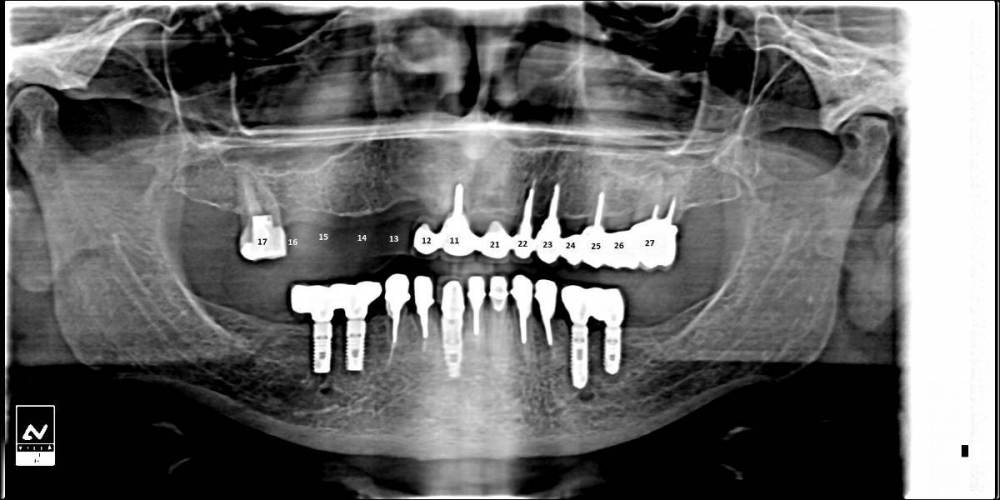

Ольга555 Опубликовано 23 августа, 2023 Поделиться Опубликовано 23 августа, 2023 Уважаемые доктора,снова обращаюсь за помощью. Консультировалась у нескольких ортопедов-хирургов,которые перед имплантацией однозначно предлагали удалить все корни на верхней челюсти и только один спросил-"Вы настроены удалить все корни,или попытаться сохранить?" Я уже настолько поверила,что сохранять нечего,что не сориентировалась с ответом,сказала -настроена удалять. Сделала орто новую,т.к КТ не получилось прикрепить из файлообменника,да и может некогда грузить докторам. На ноуте открыла только КТ в легкой версии... ничего не смогла открыть и отскринить дельного. Если по орто что то можно увидеть,какие корни можно пытаться сохранить? 27-й все озвучили сразу на удаление(все видят воспалительный процесс на КТ,про остальные как то неуверенно,но лучше удалить...над 25 был флюс,вскрывали 20 мая. Но на КТ никто не видит где он был,только визуально по шраму. Понимаю,на своем уровне,что свои корни как то поддерживают челюстную кость. 1.Можно ли в моем случае объединить мостом свои корни ,а отсутствующие зубные ряды мостами на имплантах?(это если снимать всю конструкцию) 2.Можно ли не снимая оставшийся мост,протезировать имплантами только правую сторону с отсутствующими корнями?(мост снимать,только ,если появятся проблемы) 1 Ссылка на комментарий

Bier Опубликовано 23 августа, 2023 Поделиться Опубликовано 23 августа, 2023 Здравствуйте, да и по орто видно воспаление на 27 и 25 из-за 3х зубов нет смысла что-то сохранять. Только проблем приобретете. Удалить все и одномоментно 4-6 имплантатов и нагрузка. 1 Ссылка на комментарий